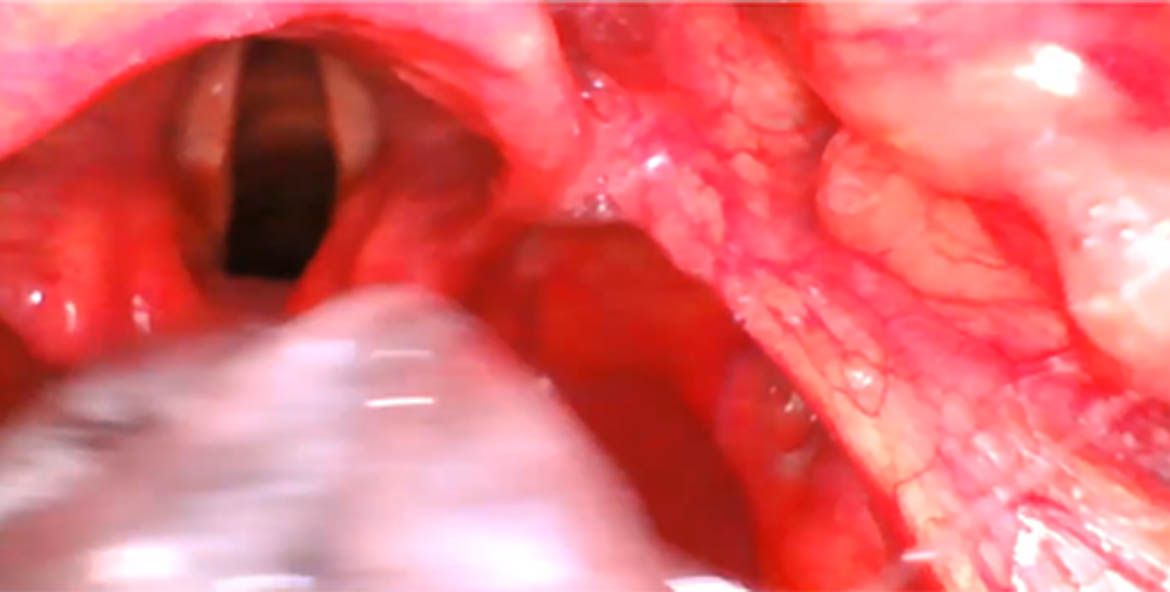

Una de las cosas que frecuentemente nos preguntamos y que a veces es una causa muy común de cuando utilizamos inicialmente los videolaringoscopios ¿por que a veces yo no puedo intubar' y les voy a presentar una serie de imágenes, en el que ustedes alcanzan a ver que tiene un perfecto cormac uno pero que al momento que ustedes introducen el tubo no lo pueden meter a las cuerdas vocales y esto porque puede ser pues por varias cosas.

2- introducimos muy profundo y aquí lo vemos en esta imagen (1) que inclusive se ve en la parte inferior el esófago y yo veo aquí las los cartílagos aritenoides y que si yo introduzco el tubo en esa forma pues irremediablemente me voy a ir a el esófago. Pero lo puedo corregir y una de las formas de corregirlo es liberar un poquito esa imagen retirar un poco y redirigir el tubo y con esta maniobra pues tenemos mucho

más éxito.

3-Choque con aritenoides Cuando yo quiero introducir el tubo y choca muy frecuente con el cartílago aritenoides éste es por lo mismo porque a lo mejor la introducción es muy profunda porque el tubo no lo monte bien en una guía o porque simplemente con el hecho de retirarse un poquito de redirigirte es la forma en la que vas a poder realizar y tener un éxito en tu intubación